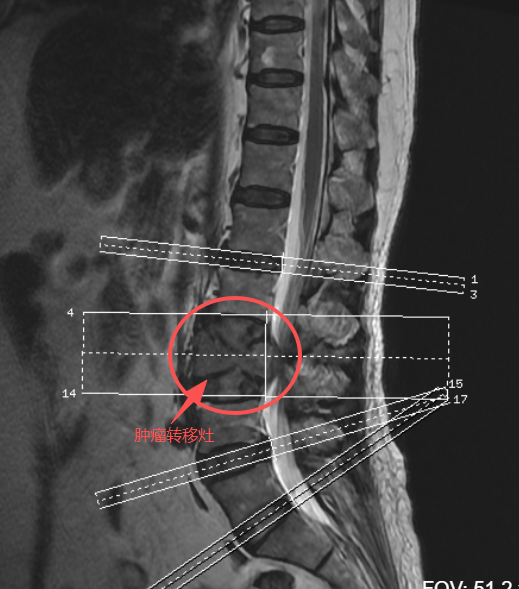

张阿姨因“腰背痛加重伴双腿疼、无力”紧急就诊,检查结果令人揪心:不仅确诊肺腺癌,癌细胞还已转移至腰椎L3椎体(支撑脊柱的重要椎体)。转移肿瘤不仅破坏椎体骨质、引发病理性骨折,还突入椎管压迫脊髓与神经,让她面临三大难题:

联合定策略:肿瘤内科、胸外科、放疗科、影像科、麻醉科等10余个科室专家会诊,确定“先手术解决腰椎危机,术后接力肺癌全身治疗”的计划;数据定范围:通过三维技术对脊柱影像进行重建与分析,精准确定肿瘤切除范围、螺钉植入位置及人工椎体尺寸;器械物料提前“备齐备好”:定制多孔钛合金人工椎体(替代L3椎体),备齐备用固定器材,术中启用“神经电生理监测”,实时预警神经损伤风险;提前准备好“救命血”:制定围手术期血液保护方案,术前备血、术中控制血压,应对可能的大出血。